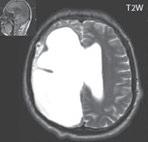

I.1.2 Ageneze, dysgeneze corpus callosum

Corpus callosum je největší komisurou (spojující stejná místa neokortexu obou hemisfér). Při narození je corpus callosum nápadně tenké (mylně někdy popisováno jako hypoplazie), i když je již většina axonů vytvořena. Jeho překotný růst je způsoben nástupem myelinizace (již vytvořených axonů). Mezi 9.–12. měsícem je vývoj tvaru i intenzita signálu corpus callosum v obrazu MR ukončena.

Často agenezi/dysgenezi corpus callosum doprovází středočárový lipom nebo cysta. Při mediálním okraji postranních mozkových komor zobrazíme Probstovy provazce, což jsou axony neuronů, které za normálních okolnosti přecházejí přes corpus callosum do druhé mozkové hemisféry. Deficit bílé hmoty mozkové okcipitálně v okolí postranních komor při absenci corpus callosum je důvodem rozšíření okcipitálních a části parietálních rohů postranních komor – colpocefalie.

Dysgeneze corpus callosum tvoří asi 4 % malformací CNS. Je součástí řady syndromů (v 50–80 % je v rámci syndromu či je asociována s dalšími malformacemi) např. Aicardiho syndrom, malformace dominantně vázaná na chromozom X (u jedinců mužského pohlaví není slučitelný se životem), dívky mají infantilní spazmy, poruchy zraku (chorioretinopatii) nebo malformace Dandy Walkerova, Chiari II. Často jsou přítomny i další malformace z poruchy migrace a gyrifikace (heterotopie šedé hmoty, schizencefalie, kortikální dysplazie...). Při hypogenezi obvykle chybí rostrum a splenium.

Zobrazení

Při agenezi corpus callosum CT i MR zobrazí paralelní průběh postranních mozkových komor (oproti fyziologickému

konvergentnímu průběhu) a jejich oddálení, časté rozšíření okcipitálních rohů – colpocefalie, někdy středočárový lipom, cystu. Koronální řezy ukážou rozšíření frontálních rohů postranních komor, III. komora je situována vysoko mezi postranní komory, tvoří jakoby trojzubec, který někteří autoři přirovnávají k přilbě Vikinga. Není patrné septum pellucidum. Častá je přítomnost středočárového lipomu nebo cysty.

Na vnitřní straně postranních komor pozorujeme v T2W obrazu poněkud tmavší strukturu než okolní myelinizovaná vlákna (naopak v T1W obrazu zvýšený signál), Probstovy provazce, axony, které za fyziologických okolností přecházejí přes corpus callosum do kontralaterální hemisféry.

Sagitální řezy nám přinášejí nejvíce informací o corpus callosum. Pozorujeme radiální průběh mozkových sulků ke stropu III. komory na vnitřní straně mozkových hemisfér a naopak nezobrazíme gyrus cinguli. Při parciální agenezi je postiženo především splenium.

Obr. I.1.2a Paralelní postavení postranních komor, kolpocefalie, ageneze corpus callosum

Obr. I.1.2b Ageneze corpus callosum

Obr. I.1.2c Ageneze corpus callosum, frontální rohy postranních komor mají tvar rohů na Vikingské helmě, kraniálně uložená III komora